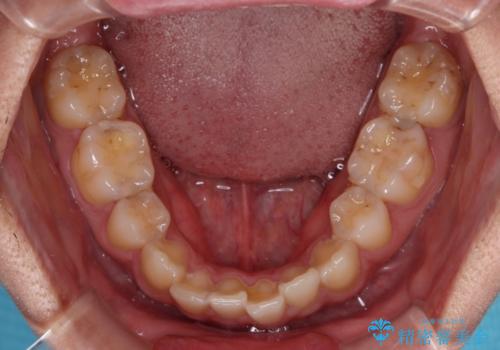

- 高校生の時に行った抜歯矯正の後戻りを気にして来院された患者様です。

インビザラインでの治療を希望されていて、デコボコの程度が中等度であり、安価なパッケージにて対応可能と判断されたため、インビザライン・モデレートを用いて矯正治療を行うこととしました。

インビザライン・モデレートは、製作できるアライナーの枚数に制限があるため、移動可能な量に限りがあるものの、インビザライン・ライトよりも枚数が多いため、幅広い症例に対応可能です。